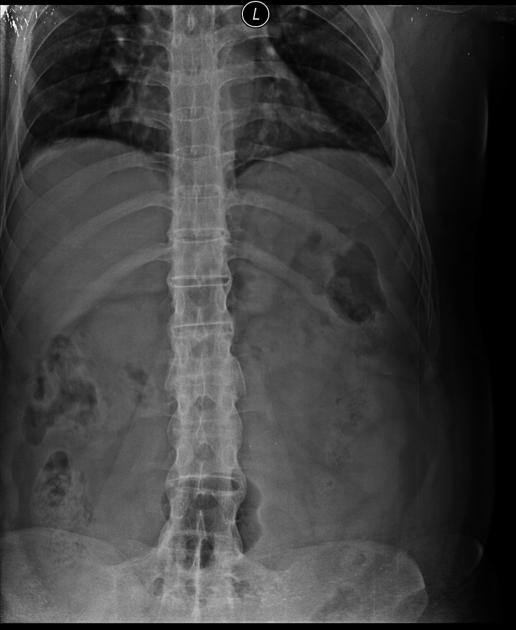

✨رسمياً اخصائية اشعة✨

✨Radiology specialist✨